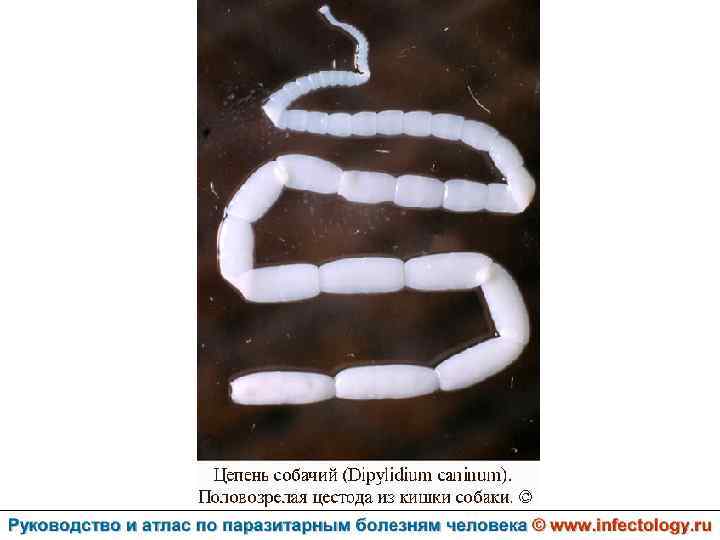

Дипилидиоз (шифр по МКБ 10 – B 71. 1) зоонозный биогельминтоз, характеризующийся аллергизацией организма и нарушением функций пищеварительного тракта.